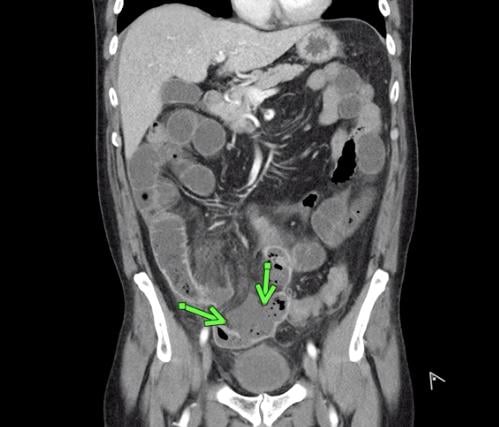

This photo gallery shows the variety of radiological presentations of COVID-19 (SARS-CoV-2) in medical imaging, including computed tomography (CT), radiograph X-rays, ultrasound, echocardiograms and magnetic resonance imaging (MRI). The radiology images show examples of typical COVID pneumonia in the lungs and the numerous complications the virus causes in the body in multiple organs, including the brain, kidneys, heart, abdomen and vascular system.

Ultrasound, especially hand-held ultrasound imaging devices, have become a primary imaging modality for novel coronavirus because of the ease to bag the device and sterilize it after use. CT and mobile X-ray systems are also used as front-line imaging systems for COVID-positive or suspected COVID patients.